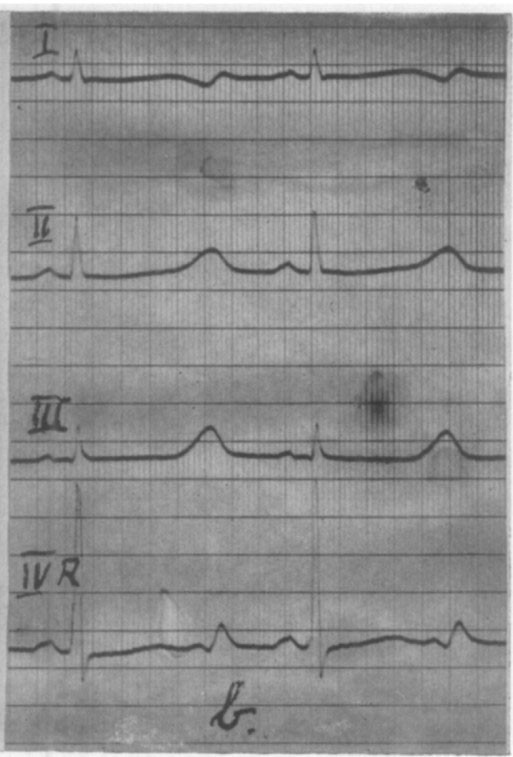

During his four-week hospital stay in Tønsberg, no abnormalities were found in the clinical examination, heart X-ray or various laboratory tests. The same change in the ECG was observed (Figure 4). No treatment was initiated (1, 21).